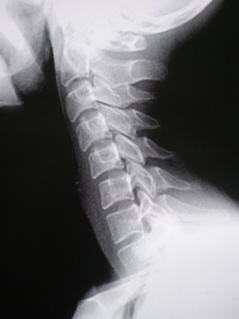

На цифровой флюорограмме, произведенной в стандартной боковой проекции (иллюстрация 1) определяется сглаженность шейного лордоза на уровне С3 - С7 с формированием патологического лордоза на уровне  С4 – С5 – С6. Определяется неравномерное сужение межпозвонковой щели в передних отделах в сегменте С4-С5.

Заключение:  Хондроз (дискоз) шейного отдела позвоночника. Нарушение статической функции шейного отдела позвоночника в виде сглаженности шейного лордоза с формированием патологического кифоза. Нарушение динамической функции шейного отдела позвоночника с нестабильностью в сегментах С2-С3, С3-С4, С4-С5, С5-С6, что свидетельствует о дистрофических изменениях в указанных межпозвонковых дисках в фазе потери их тургора.

в стандартных проекциях определяется дискоз в сегментах С4-5 С5-6. Также, имеются признаки нестабильности в С4-5.

Да, налицо "сглаженность" шейного лордоза с тенденцией формирования кифоза - желтые стрелки, следовательно дискоз имеет место быть однозначно.

Да и остеохондроз уже также имеет место быть.

Выпрямление шейного лордоза с формированием кифоза. Остеохондроз ШОП, в виде скошенности передне-верхних углов тел С4-С6 с умеренным снижением высоты м/п дисков на этом уровне.Уверен,что и унковертебральный артроз будет в прямой проекции.